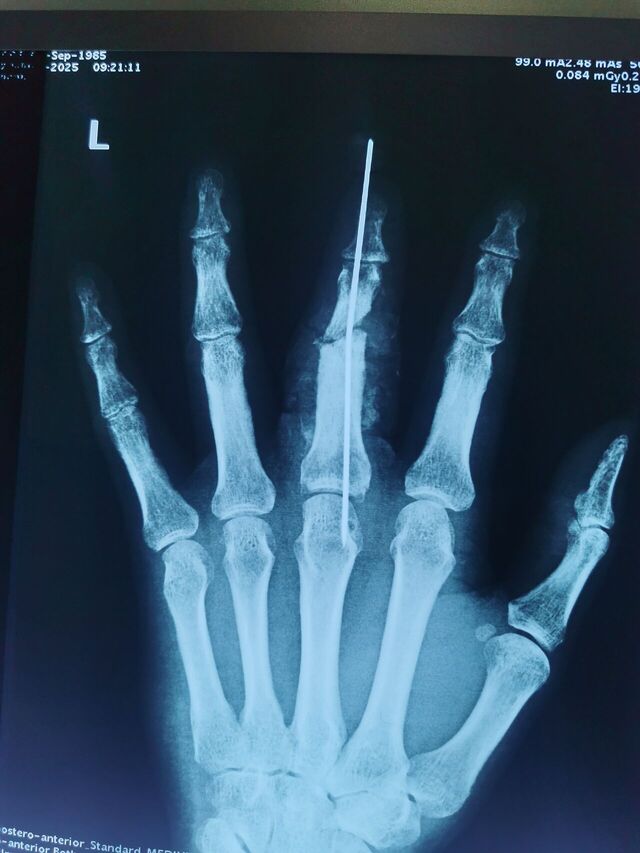

门诊的病人外院(沈阳某医院)手术的

应该是做的关节融合术

不知道如何取出克氏针

给我整不会了